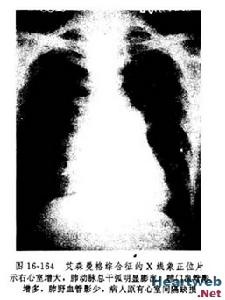

1、X線診斷心臟增大,左、右室均增大,肺動脈段凸出,肺門血管影增粗,搏動明顯,周圍血管影則纖細,此為肺動脈高壓的典型表現。